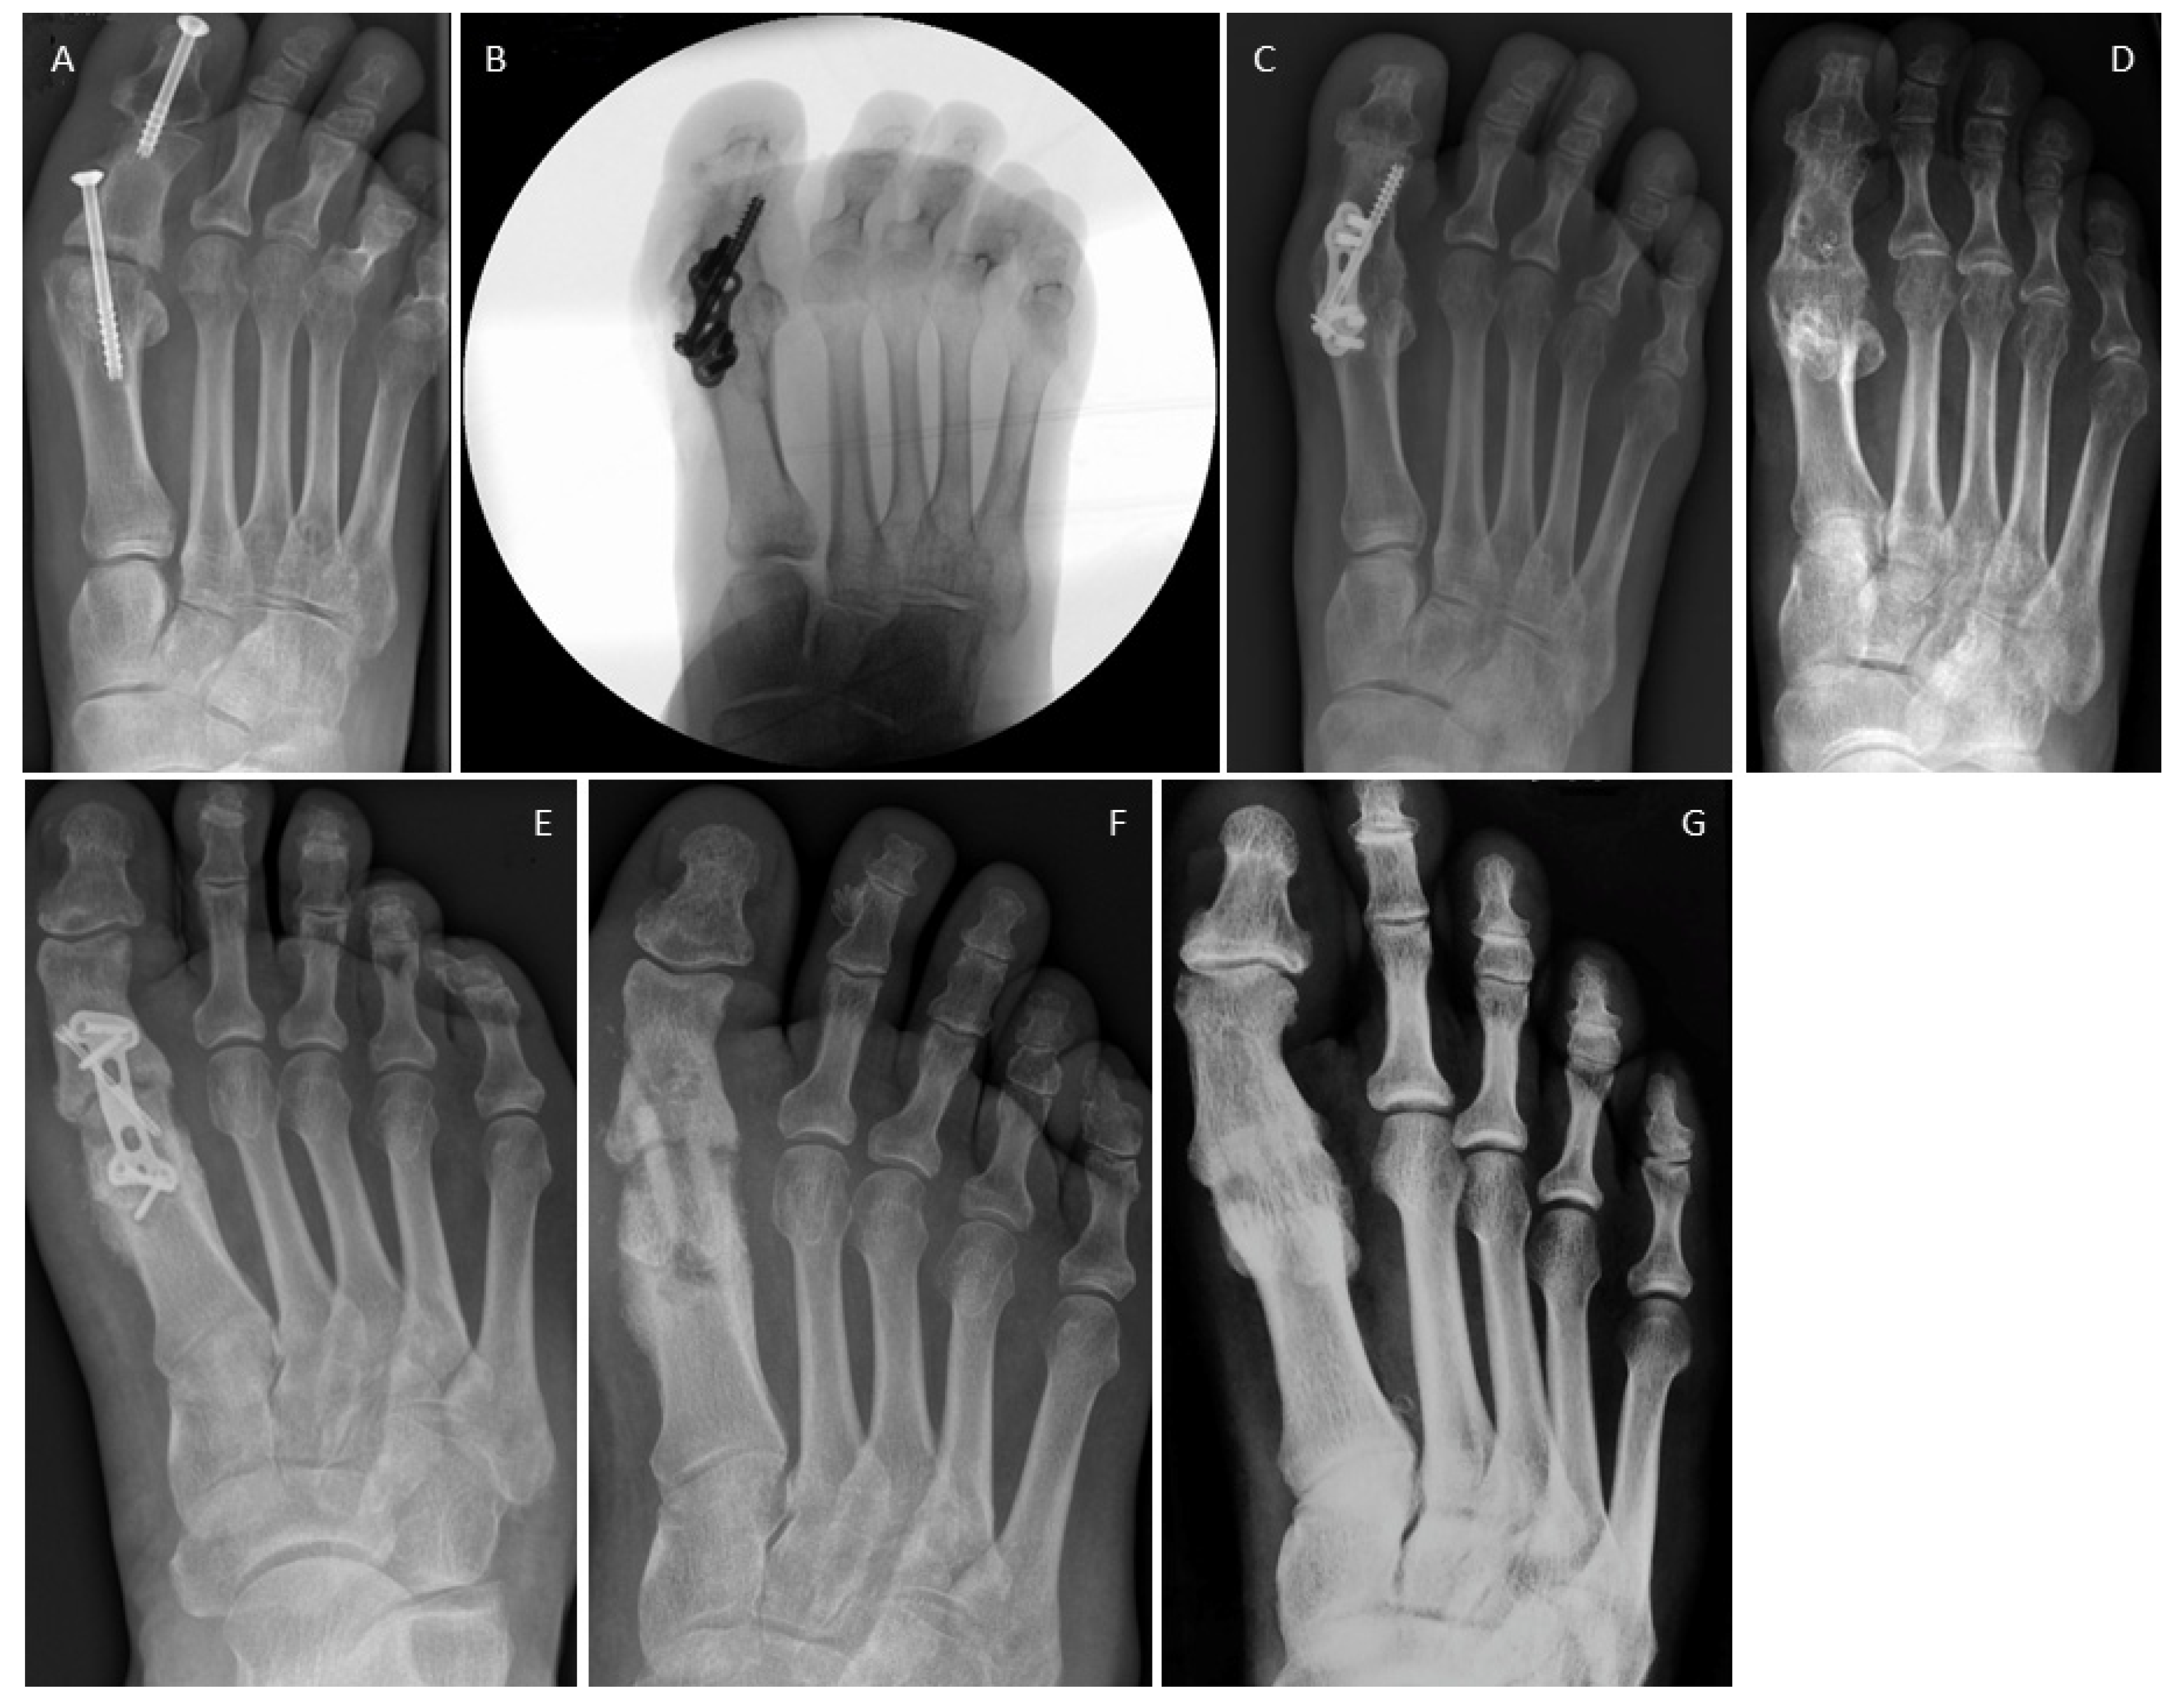

3.4. Examples for Bone Healing

3.5. Clinical Complications

3.6. Radiological Findings of Interest